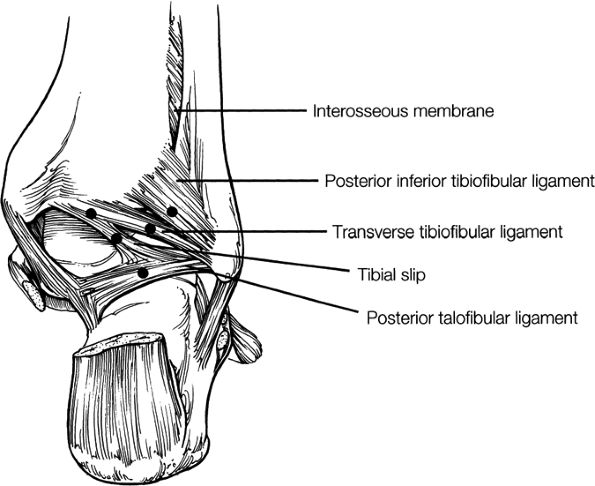

The syndesmotic ligaments consist of the anterior syndesmotic or anterior inferior tibiofibular ligament and the posterior syndesmotic or posterior inferior tibiofibular ligament, the interosseous membrane, and the transverse tibiofibular ligament.

The transverse tibiofibular ligament represents the posterior labrum of the ankle and projects inferior to the posterior tibial margin.

The tibial slip is the posterior intermalleolar ligament.